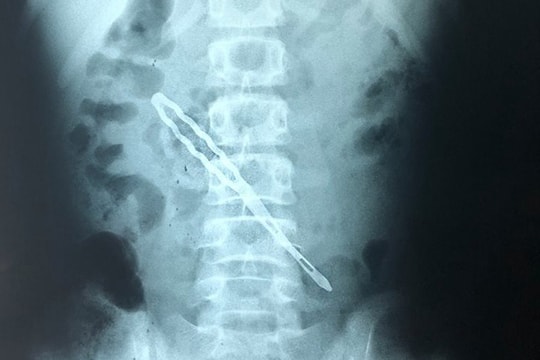

女孩吞下发夹后肠穿孔

吞下发簪四天后,这名 12 岁女孩出现严重的胃痛,并持续呕吐。